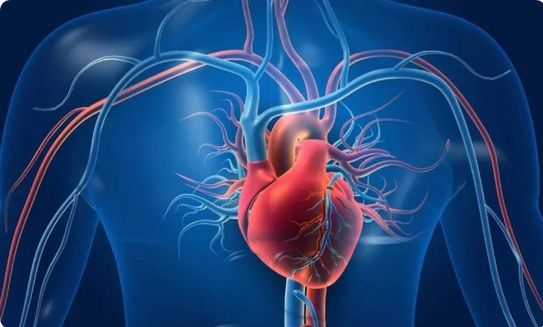

أستاذ في أمراض القلب: أغلب جلطات القلب ليست وراثية كما يعتقد البعض

نشر الدكتور خالد النمر استشاري وأستاذ أمراض القلب وقسطرة الشرايين تغريدة على تويتر قال فيها إن أغلب جلطات القلب ليست وراثية كما يعتقد البعض.

وأضاف أن هناك عدة عوامل مكتسبة قد ينتج عنها الإصابة المباشرة بجلطة في القلب منها ارتفاع الكلسترول، والتدخين، والسكري، والضغط، والتوتر النفسي، بالإضافة إلى قلة الرياضة، وقلة تناول الخضروات والفواكه.